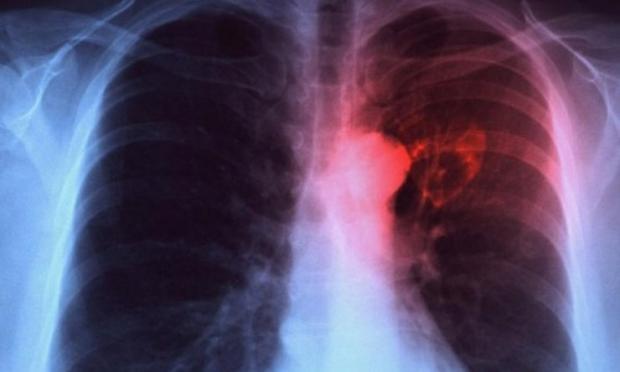

Φυματίωση: H πιο θανατηφόρα λοίμωξη παγκοσμίως – 440 περιστατικά στην Ελλάδα το 2024

Η φυματίωση παραμένει ακόμη και σήμερα η πιο θανατηφόρα λοίμωξη παγκοσμίως, πλήττοντας κυρίως τις αναπτυσσόμενες χώρες. Στην Ελλάδα, το 2024 καταγράφηκαν 440 περιστατικά, αριθμός μειωμένος κατά 19,2% σε σχέση με το προηγούμενο έτος, που ωστόσο επιβεβαιώνει ότι η νόσος δεν έχει εξαλειφθεί, σύμφωνα με το ygeiamou.gr

Παρά τη σημαντική πρόοδο της ιατρικής και την ύπαρξη αποτελεσματικών θεραπειών, η φυματίωση εξακολουθεί να αποτελεί σοβαρή απειλή για τη δημόσια υγεία. Σε παγκόσμιο επίπεδο, το 2024 καταγράφηκαν 10,7 εκατομμύρια περιστατικά και 1,23 εκατομμύρια θάνατοι, ενώ από το 2000 έως σήμερα έχουν σωθεί περίπου 83 εκατομμύρια ζωές.